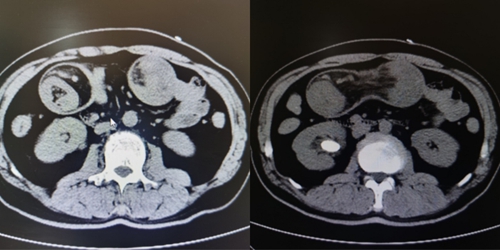

接诊后,普外科团队为李先生做了腹部CT检查,发现他患有肠套叠,需要紧急手术。同时,动漫av 胃肠外科专家王有利教授发现患者口唇周围、手和脚都长满了密密麻麻的黑色斑点,在详细询问病史后,凭借丰富的临床经验,王教授判断李先生患有一种罕见病—P-J综合征,这也是导致肠套叠的“元凶”。

动漫av 胃肠外科专家王有利教授和动漫av (青岛妇儿医院城阳院区)普外科团队紧急为李先生进行腹腔镜下空肠切除吻合术+回肠切除吻合术,手术成功,术中证实为多发p-J综合症导致的小肠多发重复套叠。目前,李先生已顺利出院。